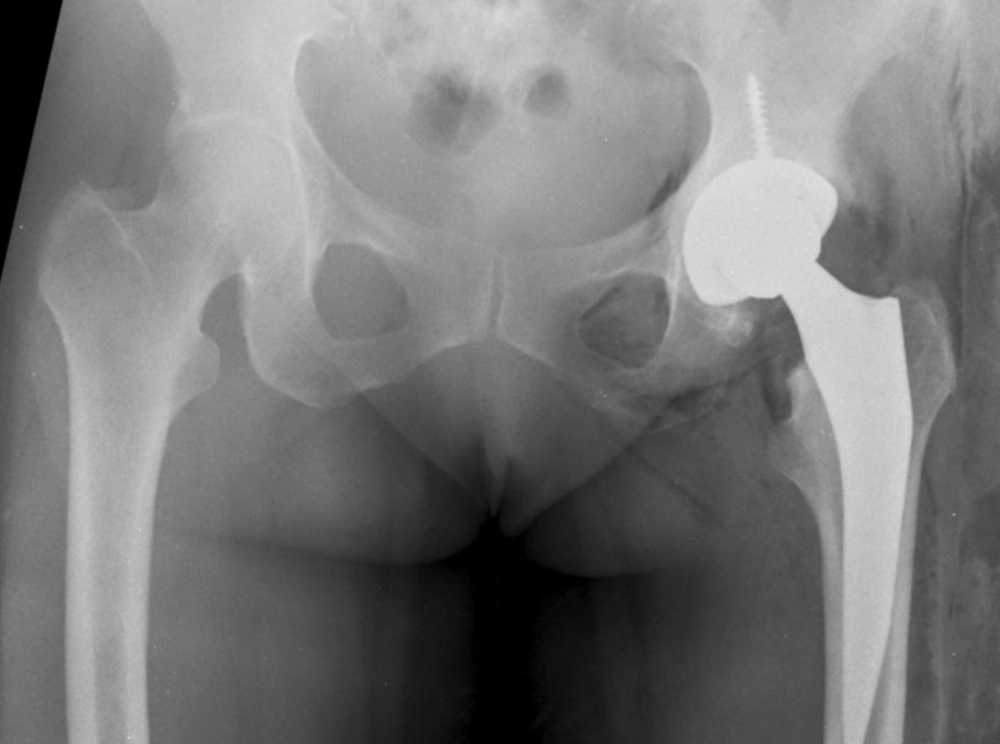

Exemplo de uma prótese total quadril esquerdo de cerâmica não cimentada.

Existem no mercado diversos modelos de prótese de quadril para cirurgias primárias e revisões. Neste artigo, irei abordar os 3 principais tipos de próteses primárias realizadas: a não-cimentada (figura 3), a cimentada (figura 2) e as próteses híbridas onde geralmente o fêmur é cimentado e o acetábulo não cimentado (figura 4). A utilização de cada uma delas depende da experiência do cirurgião e da avaliação clínica de cada paciente.